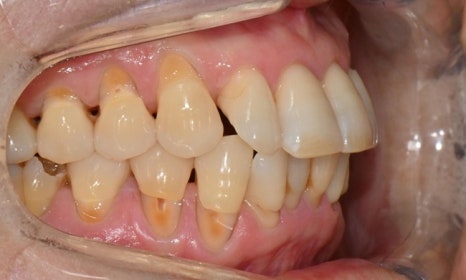

본 환자는 70세 여환으로 가만히 입을 다물고 있을 때 화난 것 처럼 보인다고 해서 튀어나온 앞니를 조금 넣고 싶다는 주소로 내원하셨습니다. 전체적인 치아 및 잇몸 상태를 검진해본 결과, 마모되어 깨진 치아도 있었고, 치경부(치아와 잇몸 사이 경계 부위)가 마모되어 파여 있는 부위도 많았습니다.

2025.2.3. 초진